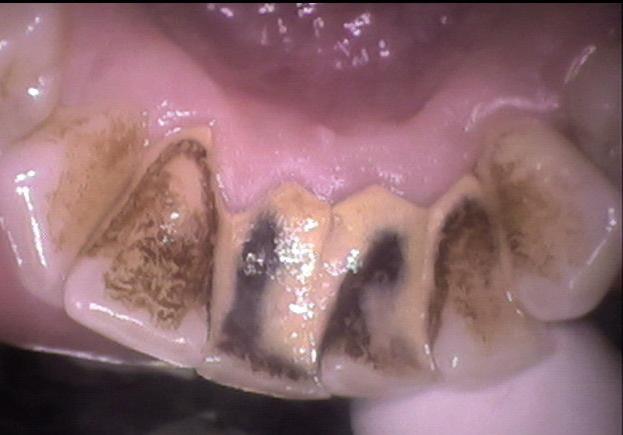

Ever wonder what happens when plaque isn’t removed regularly? These before-and-after images speak louder than words.

What you’re seeing is calculus: hardened plaque that’s fused to the teeth, picking up stains from coffee, tea, wine or smoking. It doesn’t just look bad, it traps bacteria below the gumline and fuels gum disease, bad breath and eventual bone loss if left unchecked.

This patient hadn’t seen a hygienist in years and was embarrassed by the heavy buildup. Within a couple of sessions, the transformation was dramatic - not just in appearance but in confidence too.